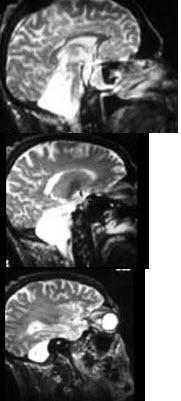

根据图示考虑是何种疾病( )

A:小脑扁桃体肿瘤

B:扁平颅底

C:Arnold-Chiari畸形

D:小脑发育不良

E:无脑畸形